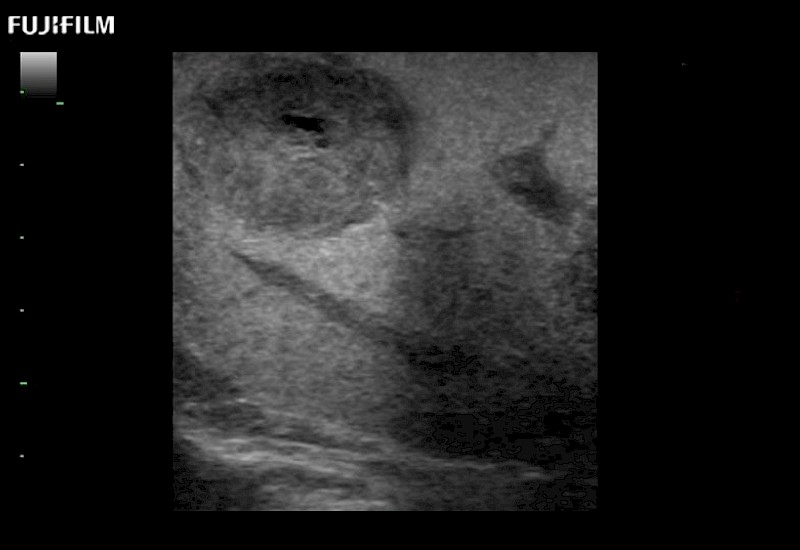

for use during open and laparoscopic procedures: Tumor localization & staging, Ablation, Resection, Biopsy, Transplant, Abdominal exploration, Robotic surgery

Our dedication to Surgical Oncology allows us to offer superior image quality, outstanding system reliability and intuitive use of cutting edge technology.